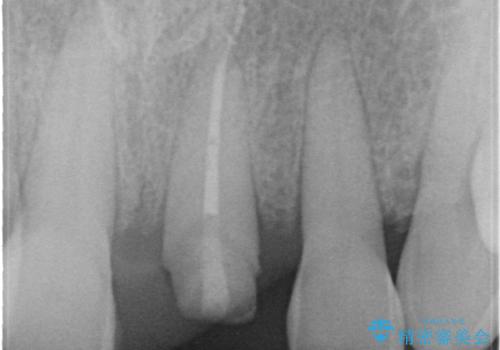

根管治療をした上で歯を引っ張りだして(エクストリュージョン)、その後、骨外科にて歯周組織を整えた上で、かぶせものを入れていく治療計画をたてました。

とても治療に対しての意識が高い方で、最初のころは歯磨きもあまりできていませんでしたが、衛生士さんの指導もあり、治療を進めるうちにプラークコントロールも改善していました。

歯を引っ張りあげたり、手術をしたあとの治り待ちをしたり、治療に時間がかかる方法ではありましたが、抜かずにその歯を使うことができたことで、患者さんにはとても満足していただけています。